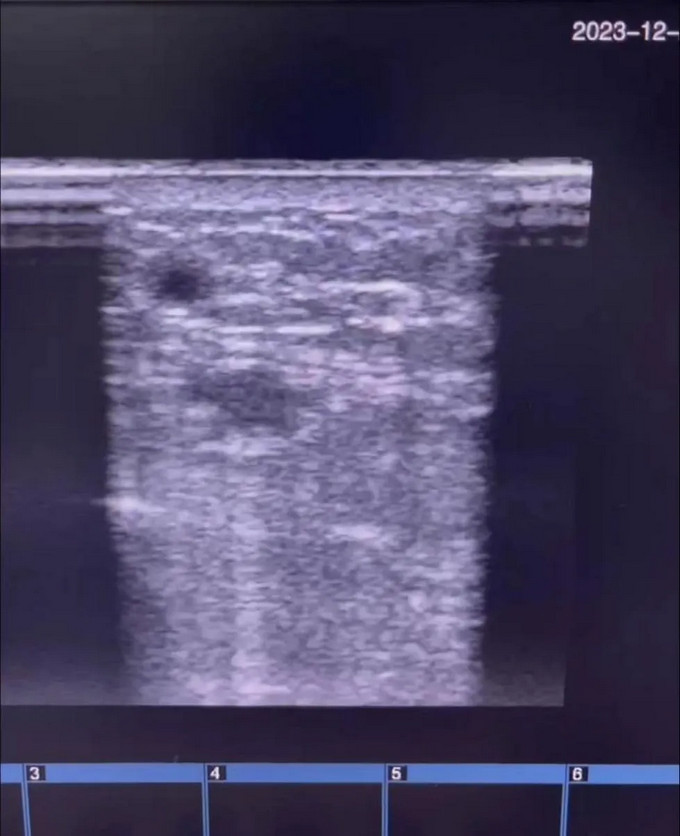

手術(shù)由腎病科張主任、李醫(yī)師完成,歷時(shí)1小時(shí),手術(shù)中張主任耐心置入導(dǎo)絲,并在導(dǎo)絲引導(dǎo)下置入擴(kuò)張球囊,經(jīng)過多次擴(kuò)張,確認(rèn)狹窄消失,血流通暢。術(shù)后超聲復(fù)查最窄血管內(nèi)徑擴(kuò)大至4.0毫米,內(nèi)瘺震顫明顯比術(shù)前強(qiáng)烈,而且手術(shù)次日便能夠穿刺內(nèi)瘺透析,血流量又達(dá)到了230ml/min,保障了血液透析的充分性。

手術(shù)后